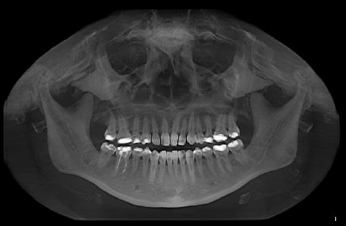

En la exploración intraoral observamos ausencia clínica del canino superior derecho y un diastema entre los dientes 12 y 14 (figura 1). Tras el estudio de la imagen panorámica (figura 2), se observa que el canino derecho superior se encuentra invertido y ubicado en la apófisis ascendente maxilar. Debido a la ubicación ectópica del diente, se solicita una tomografía axial computarizada de la estructura maxilofacial (TAC) (figura 3). Con esta ayuda diagnóstica se tendría mayor información sobre la ubicación exacta del canino derecho superior invertido (diente 13), situado en la apófisis ascendente maxilar, con respecto a las estructuras próximas o cercanas.

Por la ubicación del diente, se decide realizar el procedimiento bajo anestesia general, por lo que se coloca adicionalmente lidocaína con epinefrina local para vasoconstricción. Se procede a realizar un colgajo semilunar cercano al fondo de saco vestibular superior. Se contornea la pieza dentaria y se realiza odontosección horizontal para retirar en tres segmentos (figura 4). Se realizó una valoración para revisar el defecto dejado por el canino y no se observó una comunicación directa con seno maxilar, por lo que no se adicionaron materiales para separar cavidades. Se cierra el colgajo y se termina la intervención quirúrgica sin complicaciones. Se tomó una radiografía final (figura 5).